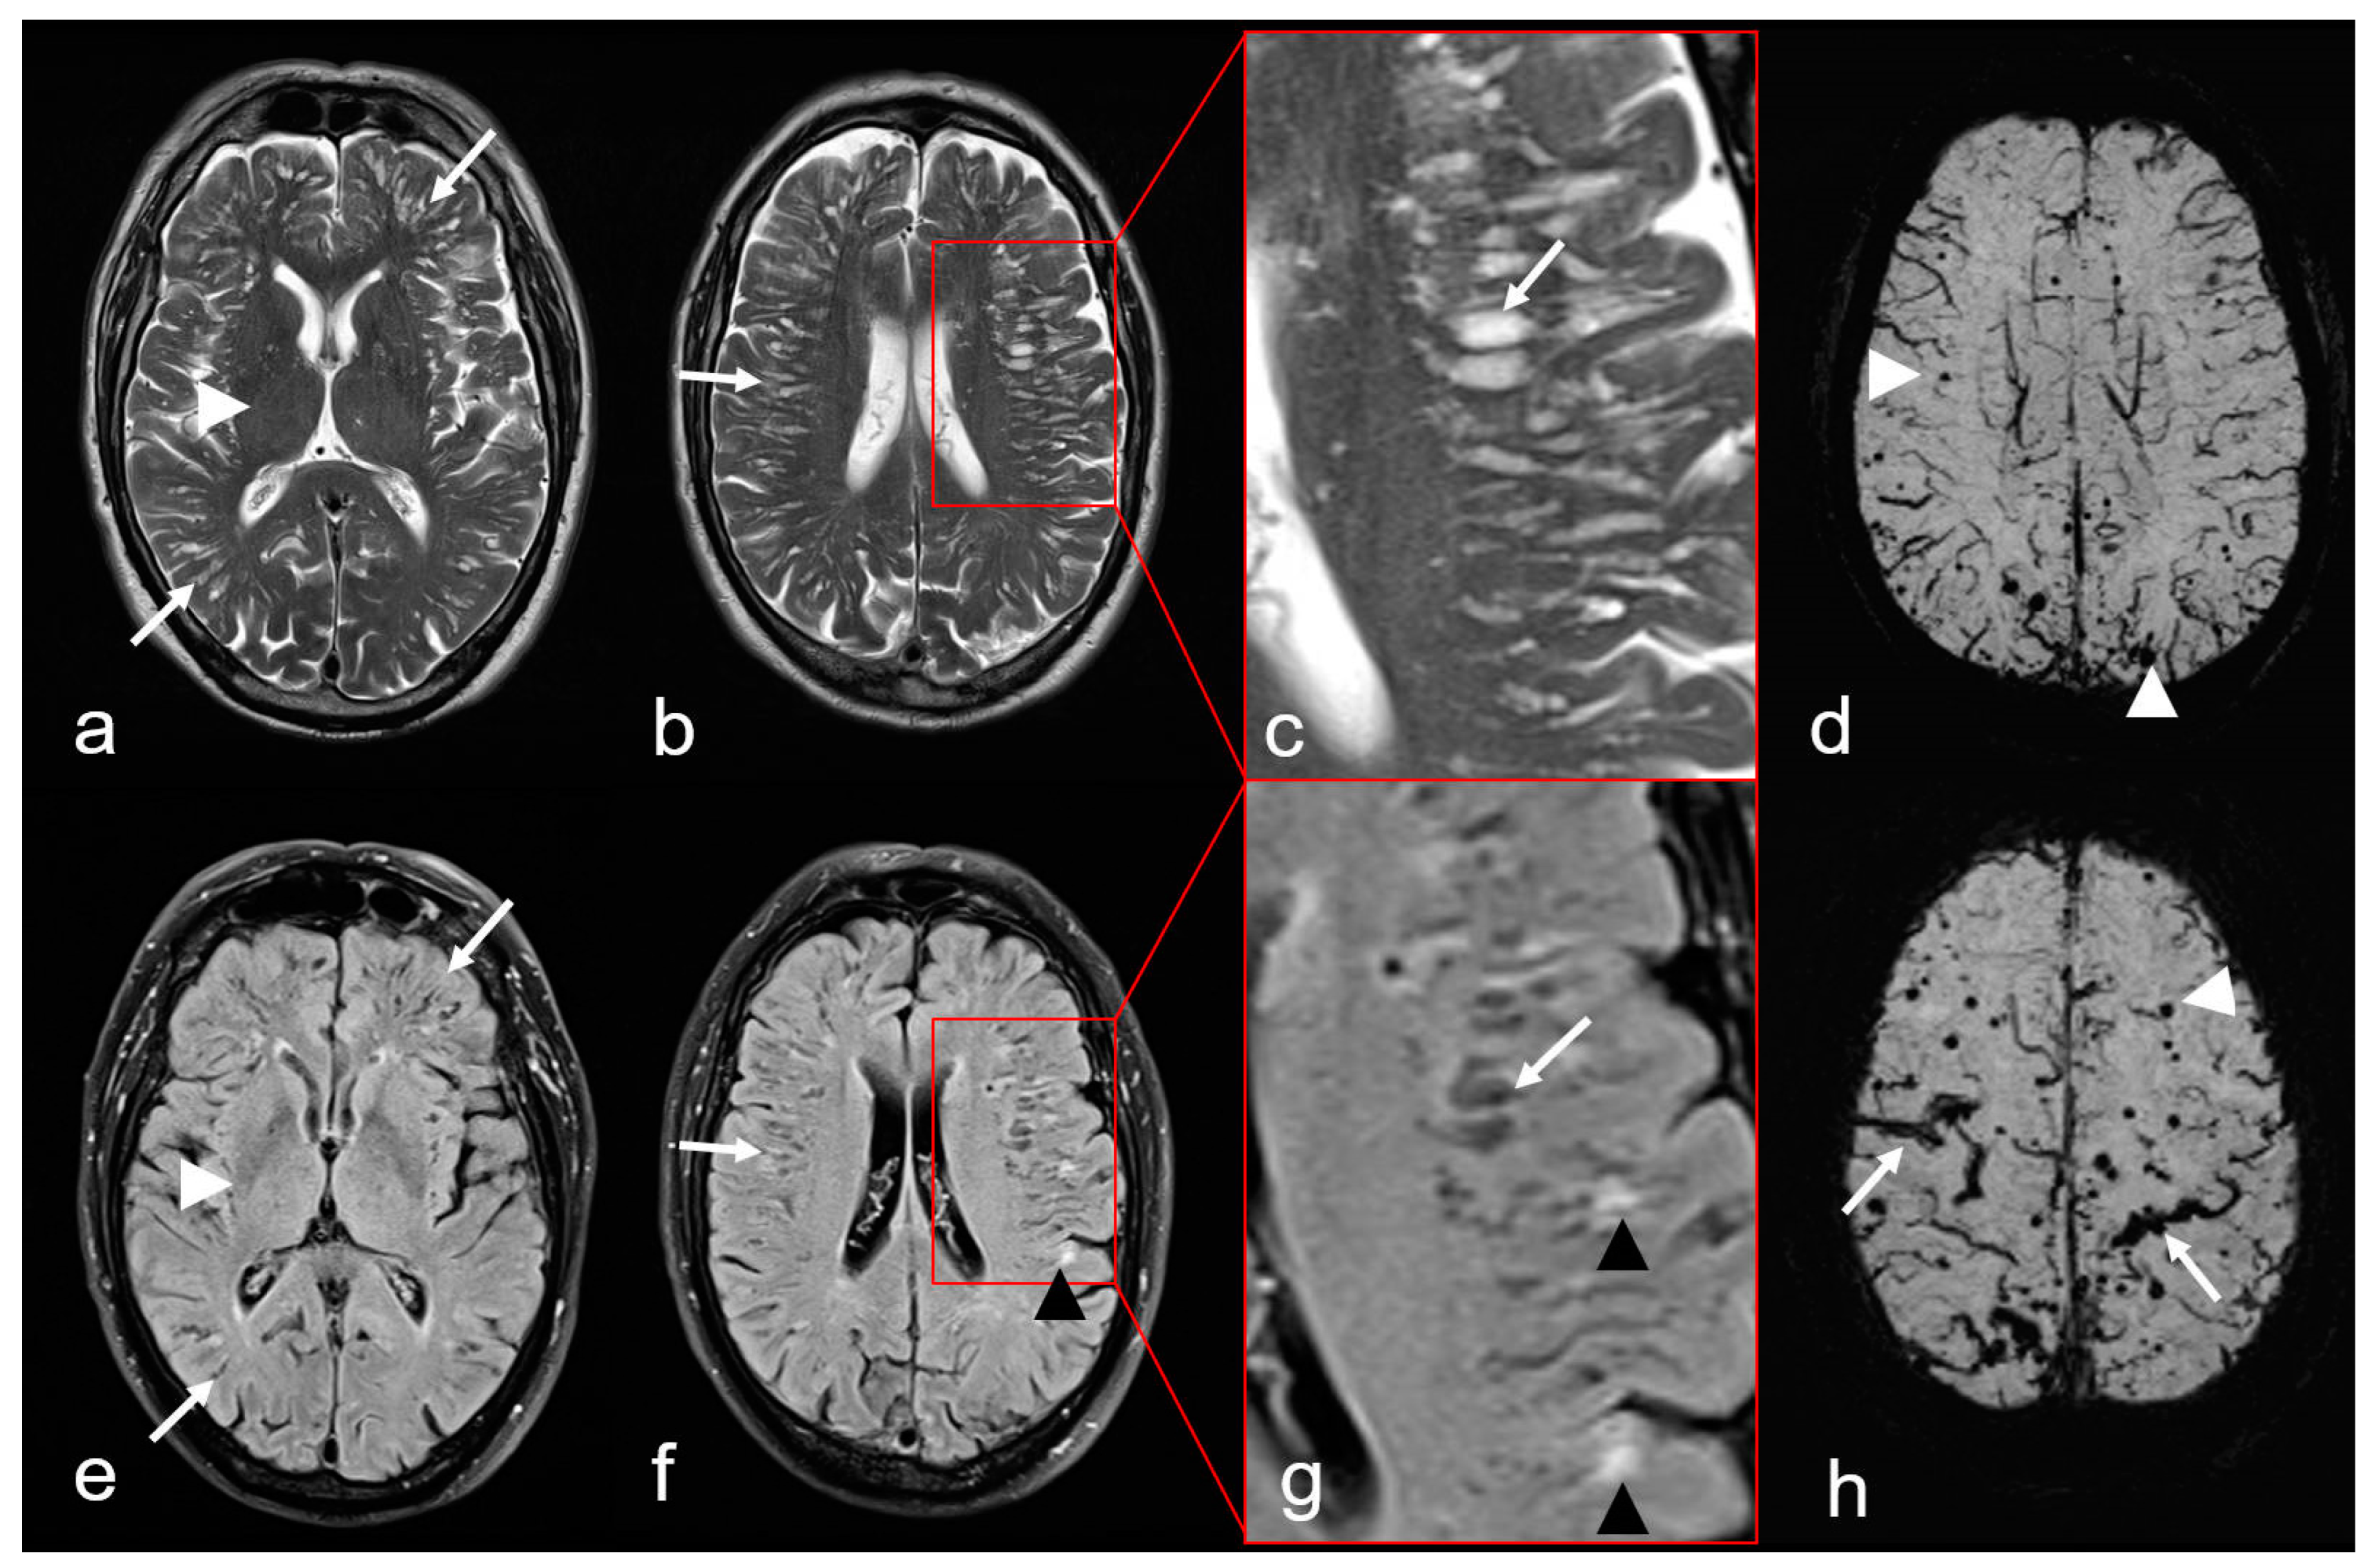

Figure 5.

Non-hemorrhagic and hemorrhagic MRI features in cerebral amyloid angiopathy (CAA). Severe enlarged perivascular spaces (PVS) supratentorial ((a–c): T2-weighted images (WI), arrow); (e–g): Fluid attenuated inversion recovery (FLAIR) images (arrow) sparing the basal ganglia ((a,e): white arrowhead), characteristic for a centrum semiovale (CSO) PVS pattern. (f,g): Multiple partially conflating white matter hyperintensities in a multispot pattern (black arrowhead, WMH-MS). (d,h): Susceptibility-weighted images (SWI) exhibit additional hemorrhagic lesions, i.e., multiple cortical/subcortical microbleeds (MB, white arrowhead) and multifocal cortical superficial siderosis (cSS; (h), arrow); MRI 1.5 T Intera, Philips Healthcare.

- The presence of enlarged PVS in the centrum semiovale (CSO), sparing the basal ganglia and thalamus, i.e., CSO PVS (Figure 5) [38,76].

- Multiple hyperintense lesions in the white matter/CSO (WMH MS: white matter hyperintensities multispot) as depicted on T2-weighted sequences (Figure 5) [38,76,77,78,79].